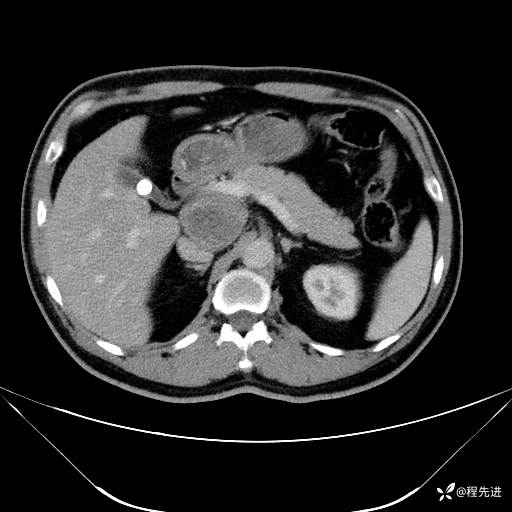

【腹盆】特别精彩病例|发现腹膜后肿物1月余

主诉:发现腹膜后肿物1月余

现病史:患者1月余前查体,行超声检查提示:后腹膜囊实性肿块;慢性胆囊炎伴胆囊内结石;无腹痛腹胀,不伴腹泻发热等;偶感腰背部酸痛。

CT平扫+增强: